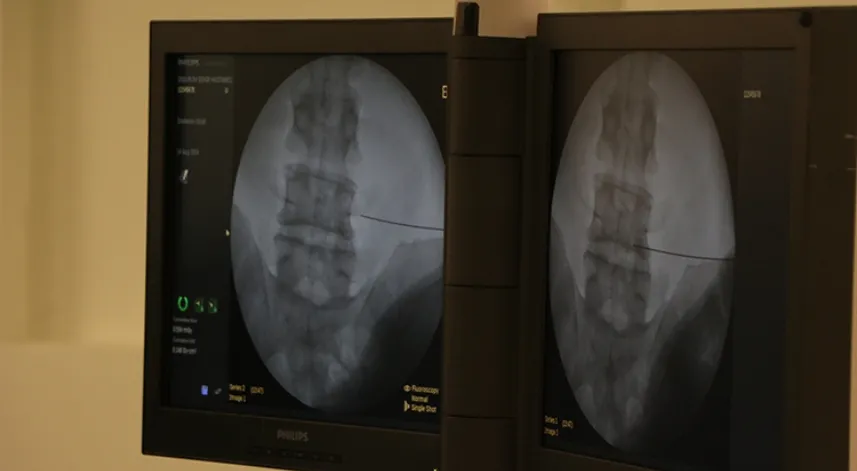

25 yaşındaki hastaya yapılan beyin tümörü ameliyatında, beynin çıplak gözle görülemeyecek deri, kemik ve beyin zarı altındaki bölgeleri, dünyada sayılı merkezde uygulanabilen karma sanal gerçeklik teknolojisi kullanılarak görünür hale getirildi.